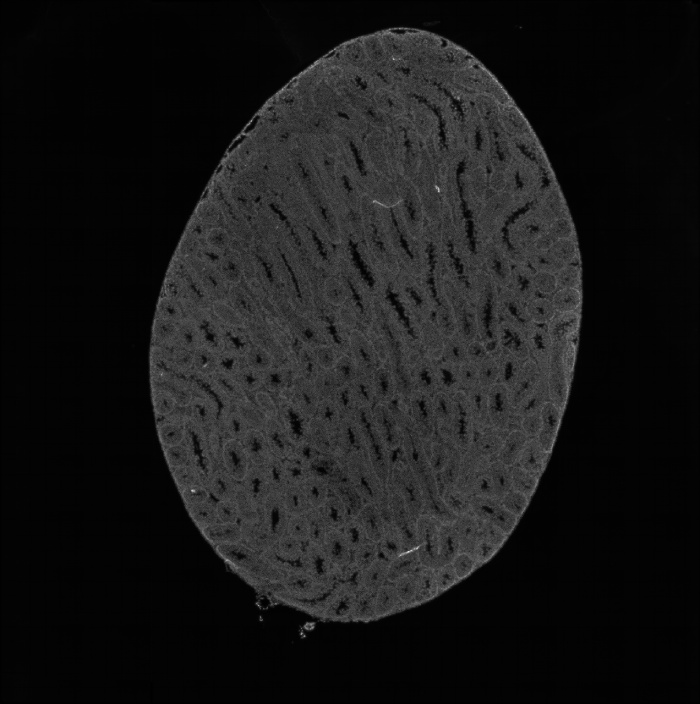

組織umi-count統(tǒng)計圖

圖2 組織UMI count統(tǒng)計圖